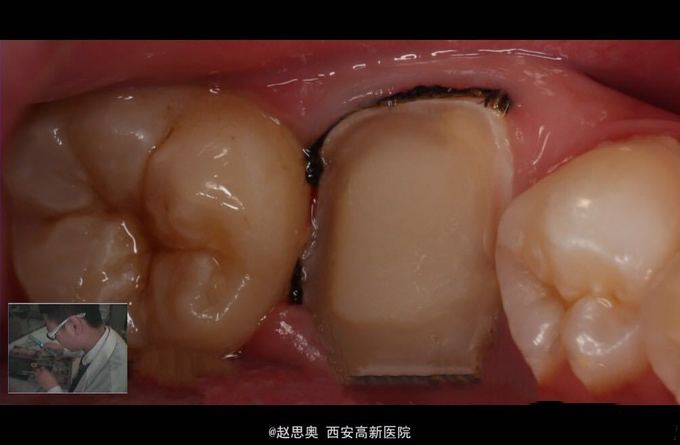

x线片示根管治疗恰填,

诊断为不可复性牙髓炎,慢性根尖周炎 处理,根管治疗后间接树脂修复